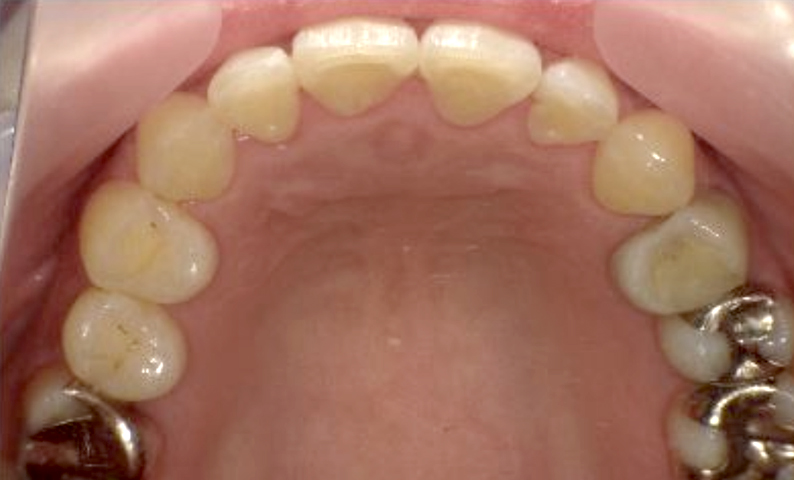

症例_003 下顎だけの部分矯正

治療期間:10ヶ月金額:24万円+税女性前歯のガタガタ下の前歯だけ上顎は補綴治療中